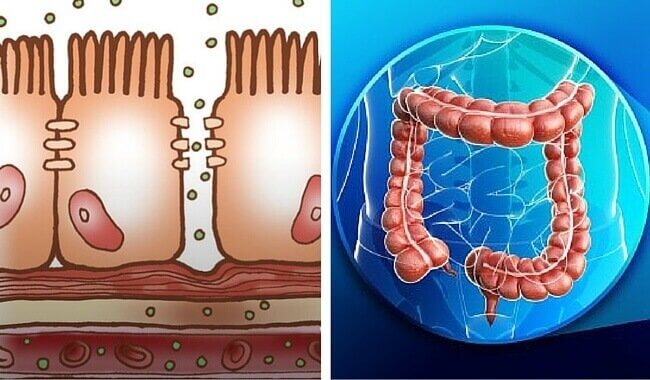

한 가지 유형의 점액이 분비물을 구성한다. 점액 분비물은 점액 세포의 직접적인 자극을 통해 형성된다. 그렇지만 골반 신경의 자극에 대한 반응도 일으킨다.

점액 분비물은 다음과 같은 3가지 기능을 갖고 있다.

- 배설물의 산으로 인한 흉터로부터 장벽을 보호한다.

- 대변을 하나로 뭉친다.

- 박테리아의 활동으로부터 장을 보호한다.

대장은 나트륨-수소 교환을 통해 능동 수송으로 나트륨을 흡수한다. 전기 기울기로 인해 일부 염소 이온은 수동적으로 세포의 내부로 이동한다. 나머지 염소 이온은 중탄산 이온으로 교환되어 흡수된다.

대장은 칼슘 또는 마그네슘과 같은 기타 이온과 함께 칼륨을 흡수하기 위해 능동 수동을 사용한다.

대장 내 세포 간의 결합은 소화관의 다른 부위보다 훨씬 더 좁다. 그 결과 이온의 역행하는 확산 작용을 막아 더 많은 나트륨을 흡수할 수 있게 된다.

알도스테론은 나트륨 흡수에 큰 도움이 된다. 결과적으로 나타나는 농도 기울기는 수분이 삼투 현상을 통해 흡수될 수 있게 한다.